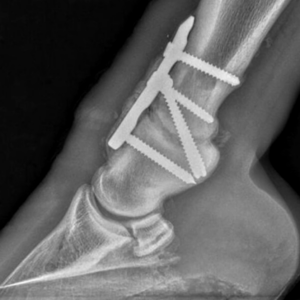

Zastosowanie płyty mostującej

Zastosowanie naszej płytki mostującej, cieszy bardzo! Pozdrawiamy specjalistów z Przychodnia weterynaryjna „Kiełbowicz” !